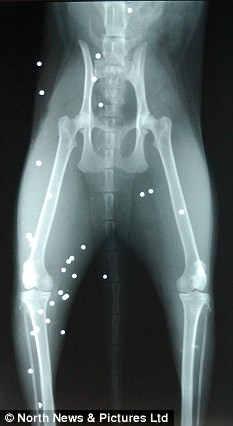

据英国《每日邮报》6月15日报道,英国一只家猫近日遭一群暴徒射击,身中50枚子弹竟奇迹般地活了下来。

<p>  两岁的猫咪罗西11日遭到了一帮社会氓流的袭击。等到主人特蕾西发现它的时候,这个可怜的小家伙正倒在血泊中,努力拖动被打瘸的后腿并痛苦地哀嚎着。“我当时惊呆了,它浑身都是血,”特蕾西说。“罗西一共有大约50处伤口,兽医取出了其中20枚子弹,剩下的30枚将永远嵌入它的身体。我太愤怒了,简直不能相信有人竟然如此残忍地对待小动物。”</p>

<p>  罗西很快接受了挽救它生命的紧急手术,它目前正在康复中。特蕾西女士已经向克利夫兰市警方报案。警方在对罗西的伤口进行分析后指出,子弹来自一把气枪,而且这种枪很可能是多枚子弹连发那种,因此猫咪当时或许是被捆绑在某个固定的位置上。</p>

<p>  兽医特纳表示:“这是我第一次救治一只被子弹击中的猫。50枚子弹对于猫而言实在太多了,可它十分幸运。”</p>